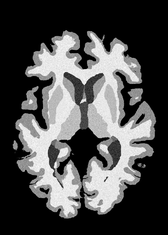

4.2 Registration to a 100 micron ex-vivo brain MRI volume

To showcase the efficacy of our method on real large scale images, we register a 250 in-vivo MRI image (Lüsebrink et al., 2017) to a 100 ex-vivo FLASH human brain volume (Edlow et al., 2019). This represents an inverse problem with more than 11.2B optimizable parameters (compared to 20M for clinical datasets), or 44.8GB of GPU memory. The entire problem does not fit on most GPUs, necessitating distributed multimodal registration. We optimize a composite transform - affine followed by a diffeomorphic mapping; details can be found in Section E.1. Multimodal deformable registration took 58 seconds on 8 NVIDIA A6000 GPUs, which is unprecedented at this resolution. Fig. 6 shows qualitative results, highlighting the ability to register highly detailed structures such as cerebellar white matter; these structures are not visible at macroscopic scales. The resultant advantages of performing registration at this scale can allow researchers to characterize the neuroanatomy at microscopic resolutions and allow morphometric analysis of cortical layers and subcortical nuclei among other structures.